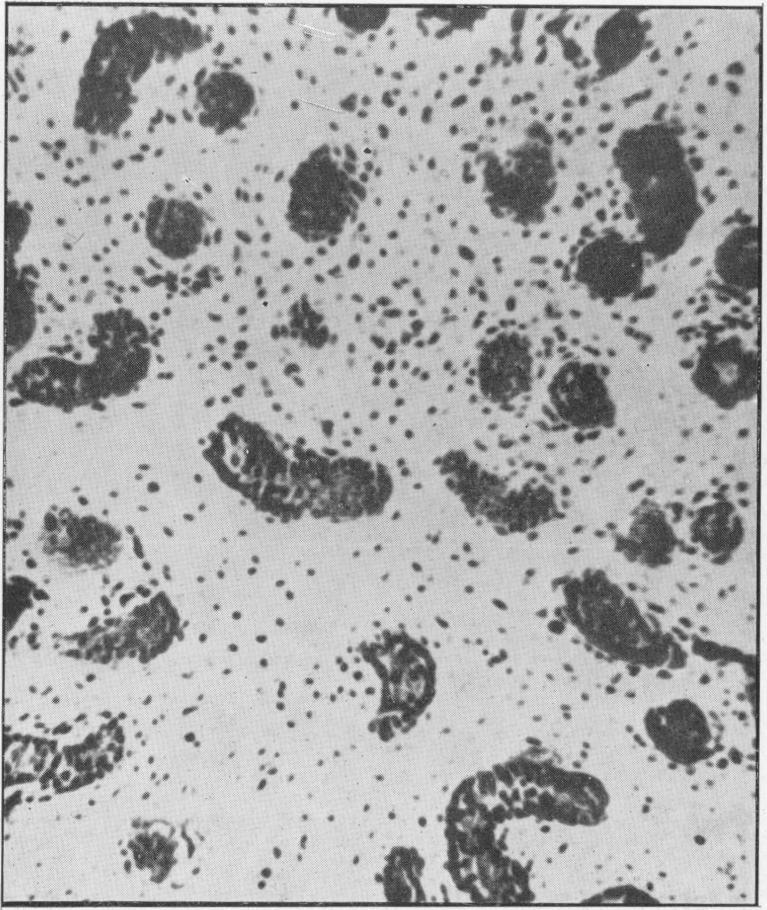

Investigations on the endocrine function of the testicle in cryptorchidism.

https://cdn.ncbi.nlm.nih.gov/pmc/blobs/15e0/2081336/a17d57953ff9/procrsmed00605-0016-a.jpg